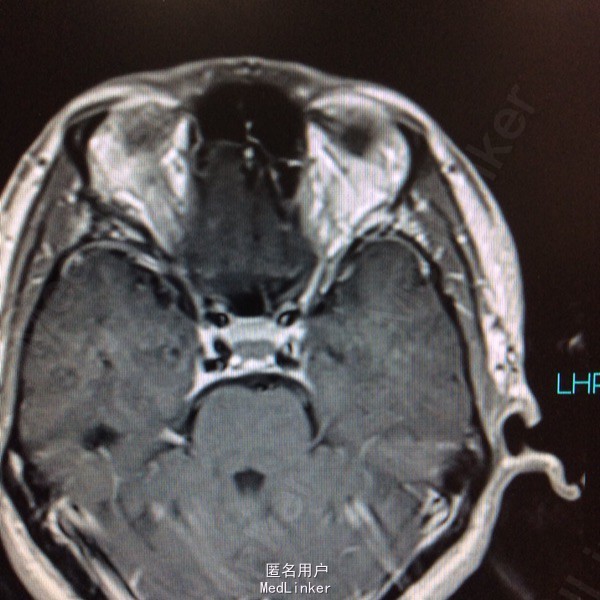

男性,31岁,头痛起病,无恶心呕吐,无视力改变。

查体未见明显阳性体征,发育正常 头颅CT提示鞍区少量出血 MRI增强提示鞍区占位病变,大小约0.8*1.5cm 考虑垂体瘤卒中

术前诊断:垂体瘤 择期行经蝶入路垂体瘤切除术 术后病理提示垂体腺瘤